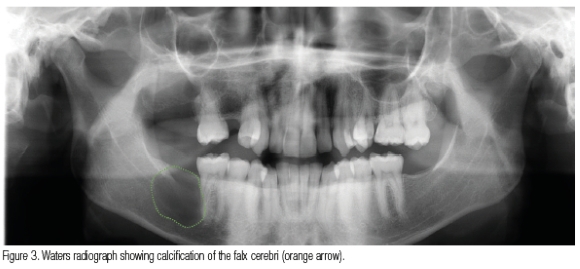

An 18-year-old male patient presented at our dental clinic in 2009 for a dental assessment. A panoramic radiograph was taken to evaluate dental crowning (Figure 1). An incidental finding was noted in the right maxilla, presenting as a well-demarcated, round, unilocular, radiolucent lesion with a corticated rim extending from the right maxillary tuberosity area to distal of the 16 causing impaction of the 18. A biopsy was taken and diagnosed as an odontogenic keratocyst (OKC) that was subsequently enucleated. In 2021 the patient returned and another panoramic radiograph (Figure 2) and a Waters view was taken where calcification of the falx cerebri was seen (Figure 3). On the panoramic radiograph an additional mandibular lesion was visible that presented as a well-demarcated, round, unilocular, radiolucent lesion with a corticated rim extending from distal of the 46 into the missing 47, 48 area. A CBCT was then taken to further analyse the lesions (Figure 4). A biopsy was taken in the right posterior mandible and diagnosed as an OKC. In 2023 the patient returned and a CBCT was taken. The right maxilla showed increased bone density adjacent to the enucleated lesion (Figure 5).

A diagnosis of Nevoid Basal Cell Carcinoma Syndrome (NBCCS) was made due to the multiple OKCs and calcification of the falx cerebri.